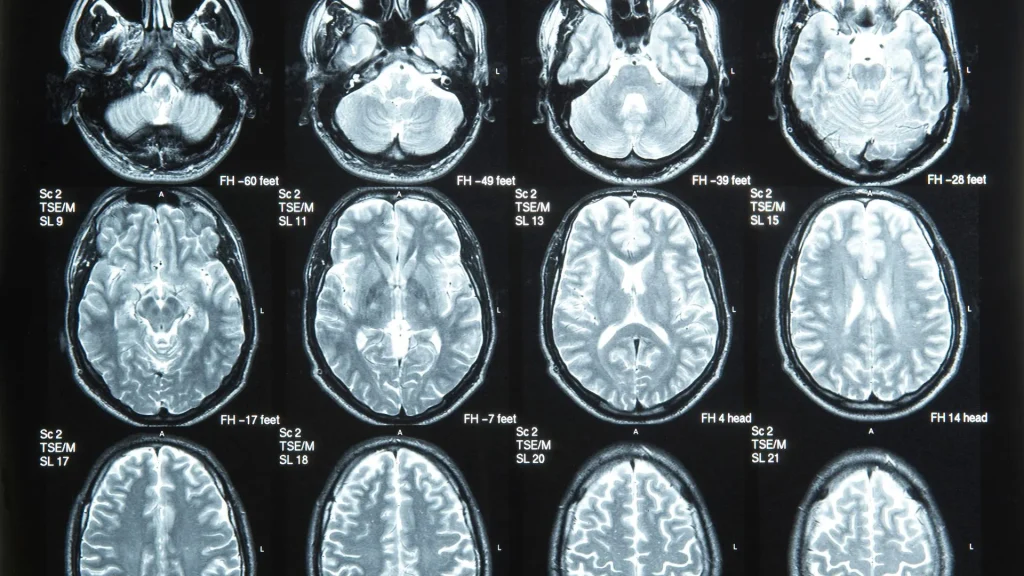

Penerapan AI dalam digital radiography memberikan dukungan analisis yang lebih cepat dan terstruktur, terutama pada pemeriksaan dada yang memiliki volume kasus sangat tinggi. Sistem AI mampu mengenali pola abnormal secara konsisten sehingga membantu dokter mengurangi beban kerja sekaligus meningkatkan ketepatan evaluasi klinis. Dengan kemampuan ini, proses identifikasi temuan awal dapat dilakukan lebih efisien tanpa mengorbankan akurasi diagnostik.

Algoritma AI dapat mendeteksi kelainan seperti infiltrat, nodul, atau konsolidasi dengan sensitivitas tinggi yang sulit diidentifikasi pada tahap awal. Teknologi ini membantu mempercepat proses penemuan penyakit paru, termasuk pneumonia, tuberkulosis, dan kanker paru. Dengan dukungan analisis otomatis, pemeriksaan rutin menjadi lebih efektif dalam menilai perubahan kecil pada struktur paru.

Teknologi AI memanfaatkan data besar dari ribuan citra dada untuk meningkatkan akurasi deteksi melalui pembelajaran berkelanjutan. Pendekatan ini membuat sistem dapat menyesuaikan diri terhadap berbagai variasi kasus dan kondisi klinis yang berbeda. Dengan basis data yang luas, kemampuan deteksi otomatis berkembang lebih cepat dibandingkan metode tradisional.

Teknologi digital radiography generasi baru menghasilkan citra berkualitas tinggi dengan noise rendah, yang sangat ideal untuk dianalisis oleh AI. Panel detektor modern memberikan detail lebih tajam, sehingga meningkatkan hasil analisis otomatis. Dengan kombinasi ini, proses diagnostik menjadi lebih kuat dan dapat diandalkan.